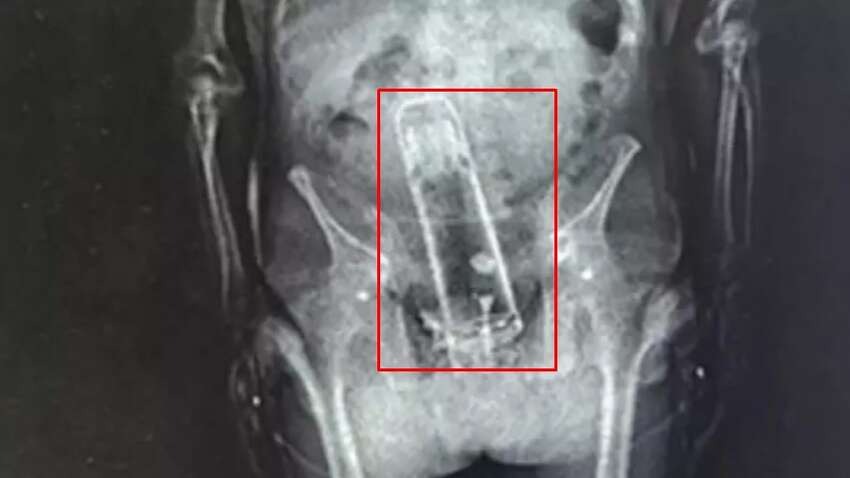

За даними американських ЗМІ, правоохоронці затримали чоловіка після повідомлення про оголеного чоловіка у туалеті одного з парків. Згодом його арештували за незаконне проникнення на залізничну колію. Коли Фраймайра доставили до в’язниці, під час стандартного рентгенівського огляду офіцери зробили несподіване відкриття. У його прямій кишці знаходився термос.

Медики в лікарні зуміли безпечно видалити термос із тіла чоловіка. За словами шерифа, це могло врятувати йому життя, адже подібні предмети можуть спричинити розриви та внутрішні кровотечі.